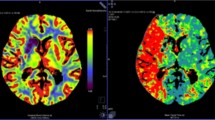

Example of individual dataset from each group of the study. From top to bottom: diffusion-weighted imaging per-occlusion and [15O]H2O perfusion PET per-occlusion; fluid attenuation inversion recovery MRI at day 7 and overlay of [11C]PK11195 DVR; fluid attenuation inversion recovery MRI at day 30 and overlay of [11C]PK11195 DVR

Visual Assessment of [11C]PK11195 PET Evolution from D7 to D30

Figure 1 illustrates representative maps of [11C]PK11195 for both the CsA and placebo group. In both groups, [11C]PK11195 DVR maps highlighted a focal increase in [11C]PK11195 uptake overlapping the lesion core, assessed by FLAIR MRI at day 7. In addition to this localized increase, we observed a diffuse [11C]PK11195 uptake that occupied nearly the entire brain. The inflammatory process also involved brain regions contralateral to the lesion side with DVR increase in both the contralateral hemisphere (cortical and subcortical regions) and the cerebellum. This global diffuse uptake was independent from the infarct size. This inflammatory pattern showed a declining trend over time but remains present in 81% of the animals (9 over 11). At day 30, the majority of the animals present a pattern of sustained focal inflammation, sometime alongside with a lower diffuse [11C]PK11195 uptake (Supplemental Fig. 3 for additional DVR maps).